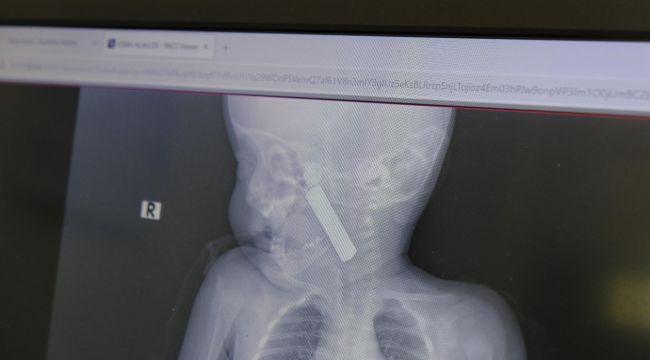

Edinilen bilgiye göre, kusma şikayeti ile ailesi tarafından Karaman Eğitim ve Araştırma Hastanesi acil servisine getirilen 6 aylık E.A. isimli kız bebeğin, yapılan muayene ve tetkiklerde boğazında kumanda pili kaçtığı tespit edildi. Solunum sıkıntısı da yaşayan bebek hemen ameliyata alındı. Çocuk Cerrahisi Uzmanı Doç. Dr. Mehmet Uysal tarafından yapılan ameliyatla bebeğin boğazındaki pil çıkarıldı.

Yaşanan olayla ilgili bilgi veren Doç. Dr. Mehmet Uysal, "Acil polikliniğimize kusma şikayeti ile 6 aylık bir kız bebek getirilmiş ve bize haber verildi. Biz de vakit kaybetmeden geldik, hastamızı gördük. Yapılan tetkikler sonucunda, ağız tabanına oturan ve yemek borusunun birinci darlığına kadar uzanan, kumanda pili dediğimiz bir pille karşılaştık. Filmde ve muayenede bunu gördük. Hastayı ilk gördüğümüzde bayağı siyanotik durumda, solunum sıkıntılıydı ve oksijen satürasyonu 90 civarındaydı. Böyle olunca bir an önce beklemeden hızlı bir şekilde ameliyathaneye götürdük. Orada ameliyathanedeki anestezi uzmanlarımız ve personel bize yardımcı oldu, hasta hızlı bir şekilde entübe edildi. Ondan sonra da laringoskop ve magill forseps dediğimiz malzemelerimizle bu yabancı cismi çıkarmış olduk. Bir an evvel müdahale ettik, iyi ki müdahale ettik, orada ağız tabanında, özellikle ön kısmında hasar oluşmuştu. Müdahale sonrasında da hastanın solunum problemleri bir süre devam etti, bu yüzden 24 saat takip ettik. Herhangi bir problem oluşmayınca 24 saat sonra kontrole gelmek üzere hastayı taburcu ettik" diye konuştu.